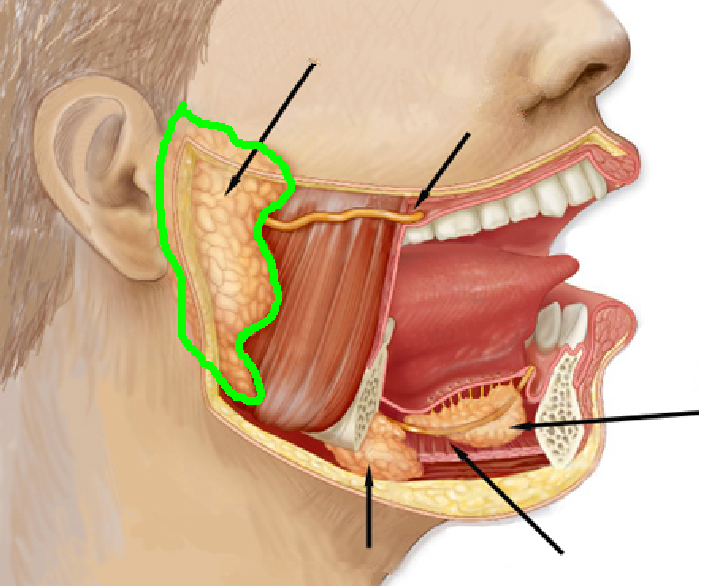

Genioglossus

Hyoglossus

Palatoglossus

Styloglossus

Parotid gland

Parotid duct

Submandibular gland

Submandibular ducts

Sublingual gland

Sublingual ducts